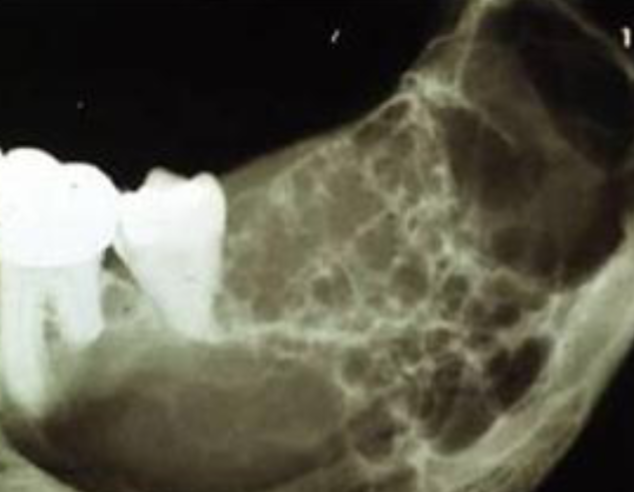

multilocular and well-defined

how would you describe this lesion?